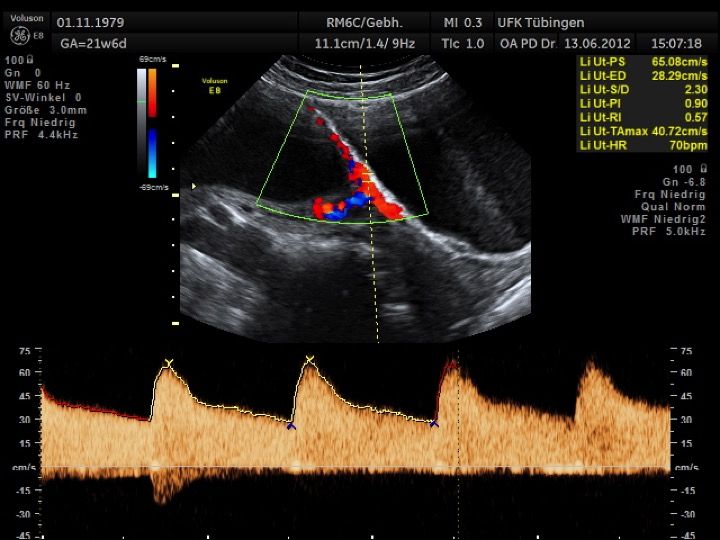

Mithilfe des Ersttrimester-Screenings kann das persönliche Risiko einer Präeklampsie bestimmt werden. Dazu wird die Vorgeschichte der Schwangeren, der aktuelle Blutdruck, das Ergebnis der Ultraschalluntersuchung (Widerstand in den Gebärmutter-nahen Gefäßen) und der Blutabnahme bei Ihnen (PAPP-A) kombiniert. Sollte das Risiko über 1:100 sein, empfehlen wir die tägliche Einnahme von Aspirin 150mg bis zu 35.SSW und eine gezielte Überwachung der weiteren Schwangerschaft.

Auch hier gilt wieder, dass der Untersuchung eine Aufklärung und Beratung vorausgeht und die Ergebnisse nach Abschluss der Untersuchung ausführlich besprochen werden.